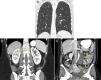

Lymphangioleiomyomatosis (LAM) is a rare interstitial lung disease that mostly affects women, and is characterized histologically by the proliferation of atypical smooth muscle cells in the lymphatic system. Radiologically, LAM in the lung parenchyma is characterized by the presence of multiple pulmonary cysts (Fig. 1a). Abdominal findings associated with LAM are less well known, although they have been described in up to 70% of patients. The most common is renal angiomyolipoma (AML), which can appear in 20%–54% of cases. Other findings are lymphangioleiomyomas, lymphadenopathies and chylous ascites.1

The first case is that of a 42-year-old woman who presented clinically with a pneumothorax that required a chest drain. During the same procedure, cysts were removed from the apex of the lung, with a histological diagnosis of LAM cysts. A subsequent chest computed tomography (CT) incidentally detected a right renal mass (Fig. 1b). The mass was exophytic, with homogeneous density, measuring about 4-cm, and did not contain fat. Radiologically, it corresponded to an indeterminate renal mass, but given that the patient had already been diagnosed with LAM, and that fat was not evident within the mass, it was suggested that it could be consistent with an atypical AML. A percutaneous biopsy performed to rule out any other type of renal tumor confirmed that it was indeed an AML. The patient remains asymptomatic as regards the renal mass, and is undergoing checkups.

The second case is that of a 38-year-old woman in whom suspected cancerous ovarian cysts were detected during a gynecological examination. On the abdominal CT for staging and diagnosis, multiple round cystic lesions were observed in the retroperitoneum and pelvis (Fig. 1c). Pulmonary cysts were seen in the lung bases. The patient had no respiratory symptoms. Radiologically, the retroperitoneal and pelvic cysts were consistent with lymphangioleiomyomas, and the finding of cysts in the lung parenchyma confirmed the diagnosis of LAM. In this case, the disease presentation was the abdominal findings.